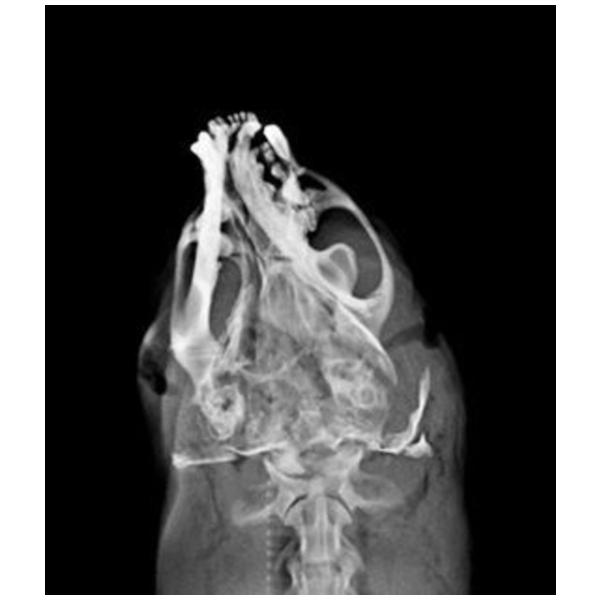

編號D105002水獺。成年雄性可見睪丸,體重5.95Kg,身長106cm、胸徑36.5cm,口鼻流大量鮮血,受理時仍為溫體但已無呼吸心跳。X光檢查頭骨粉碎性骨折、下頷骨骨折、肺前葉出血。死因判定為強烈外力撞擊頭部造成死亡。